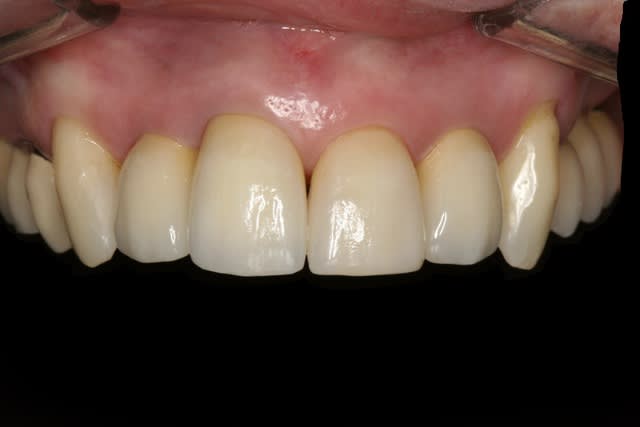

La suite avec les deuxièmes provisoires en places, le projet esthétique étant validé, les emp. ont été réalisées, ceramo-metal sur moignon composite a venir..